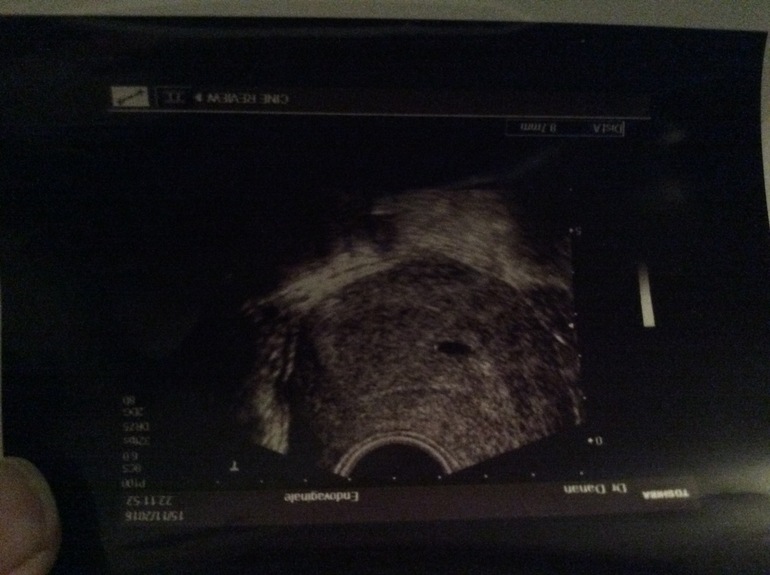

Беременность, признаки по БТ, есть ли шанс?Позавчера была у Г , сделал узи и сказал скорей всего Б , у меня О была на 24 дц , и по этому сказал что очень маленький и надо было сдать ХГЧ , вчера сдала / ответ отрицательный . К врачу попаду в панидельник.Сегодня начались розовые выделение.Наверно это врач что то ни то увидел ? У кого так было ?

Вы знаете узи вещь такая.. Если узист корявый, то многое можно не увидеть. Но на фото даже я вижу. Сходите к другому специалисту, может он подскажет